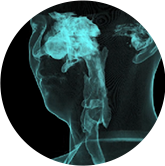

气道

气道三维影像重建